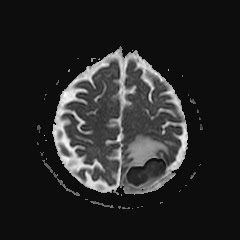

Caso neurorradiología

Paciente de 60 años con cuadro de 1 semana de evolución consistente en tropiezos frecuentes y alteración en la movilidad del miembro

inferior derecho. No refiere

cefalea u otros síntomas asociados, no pérdida de peso, no náuseas o emesis, no

sudoración nocturna. Antecedentes de hipertensión arterial y diabetes.

Escanografía